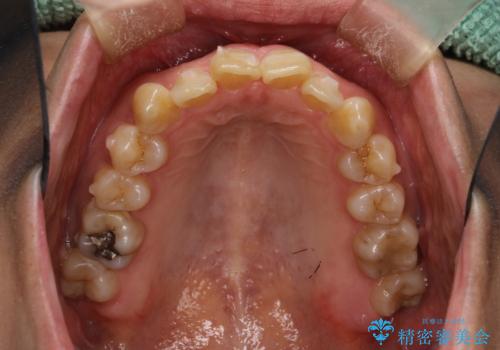

- 上下の歯並びにガタつきがあり、また、上下前歯の前後のズレが大きく上の前歯が突出しています。

インビザラインではガタつき(叢生)の改善だけでなく、上下の前後的なズレについてもアプローチが可能です。

インビザラインの特色を生かした歯牙移動計画を作成し、非抜歯にて治療を行いました。